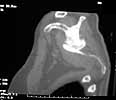

61 yo male 5 months post motorcycle crash. He had "floating shoulder" & flail chest. Pulmonary problems prevented any early intervention. He now has quite severe pain with scapular motion. Would appreciate thoughts on dealing with this. I don't think clavicular osteotomy and restoration of clavicular length will help. His pain seems to be coming from the area where his scapula crosses the significantly deformed ribs.

Consider - Missed scapular fracture after trauma. A case report and a 23-year follow-up report. Clin Orthop. 1994 Feb;(299):259-62.

Can preop planning be assisted by actual 3D models produced by stereolithography or other rapid prototyping techniques reported by Brown et al - OTA 2002. ??